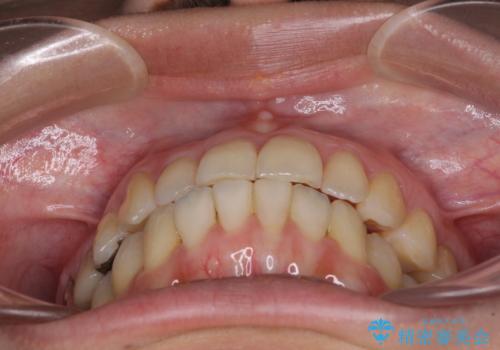

切端咬合をインビザライン矯正で解消

上下前歯の先端同士が接触する切端咬合であったため、上顎は歯列を拡大し、下顎はIPR(歯と歯の間を削る)により叢生を解消しながら歯列を小さくすることとしました。

切端咬合はスムーズに解消され、前歯の負担を軽減させることができました。